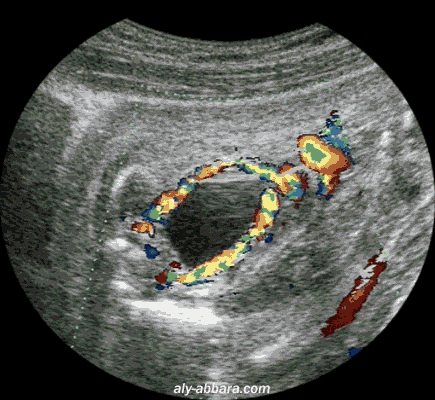

Les artères ombilicales coiffant la vessie dans leurs trajets pelviens

(grossesse de 22 SA)

Cette exploration permet de faire le diagnostic différentiel entre la vessie fœtale et une masse kystique pelvienne